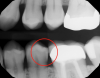

Fig 12. Nothing problematic visible on x-ray.

Figure 12

Fig 13. Transillumination image showed fracture on tooth No. 19.

Figure 13

In yet another case, a comparison of an x-ray and a transillumination image is presented in Figure 12 and Figure 13. Though nothing was visible on the x-ray, the transillumination image showed a total fracture through the buccal cusp on tooth No. 19 that would require a crown. An added benefit is that the transillumination image can be used for the insurance predetermination. Figure 14 and Figure 15 depict a case of a lingual fracture on tooth No. 3 where nothing problematic showed up on the x-ray. However, the transillumination image showed the facture as well as caries distal to the fracture (Figure 16). There was also recurrent decay adjacent to the restoration. The image made the problem obvious to both the clinician and the patient, which led to the patient accepting treatment.